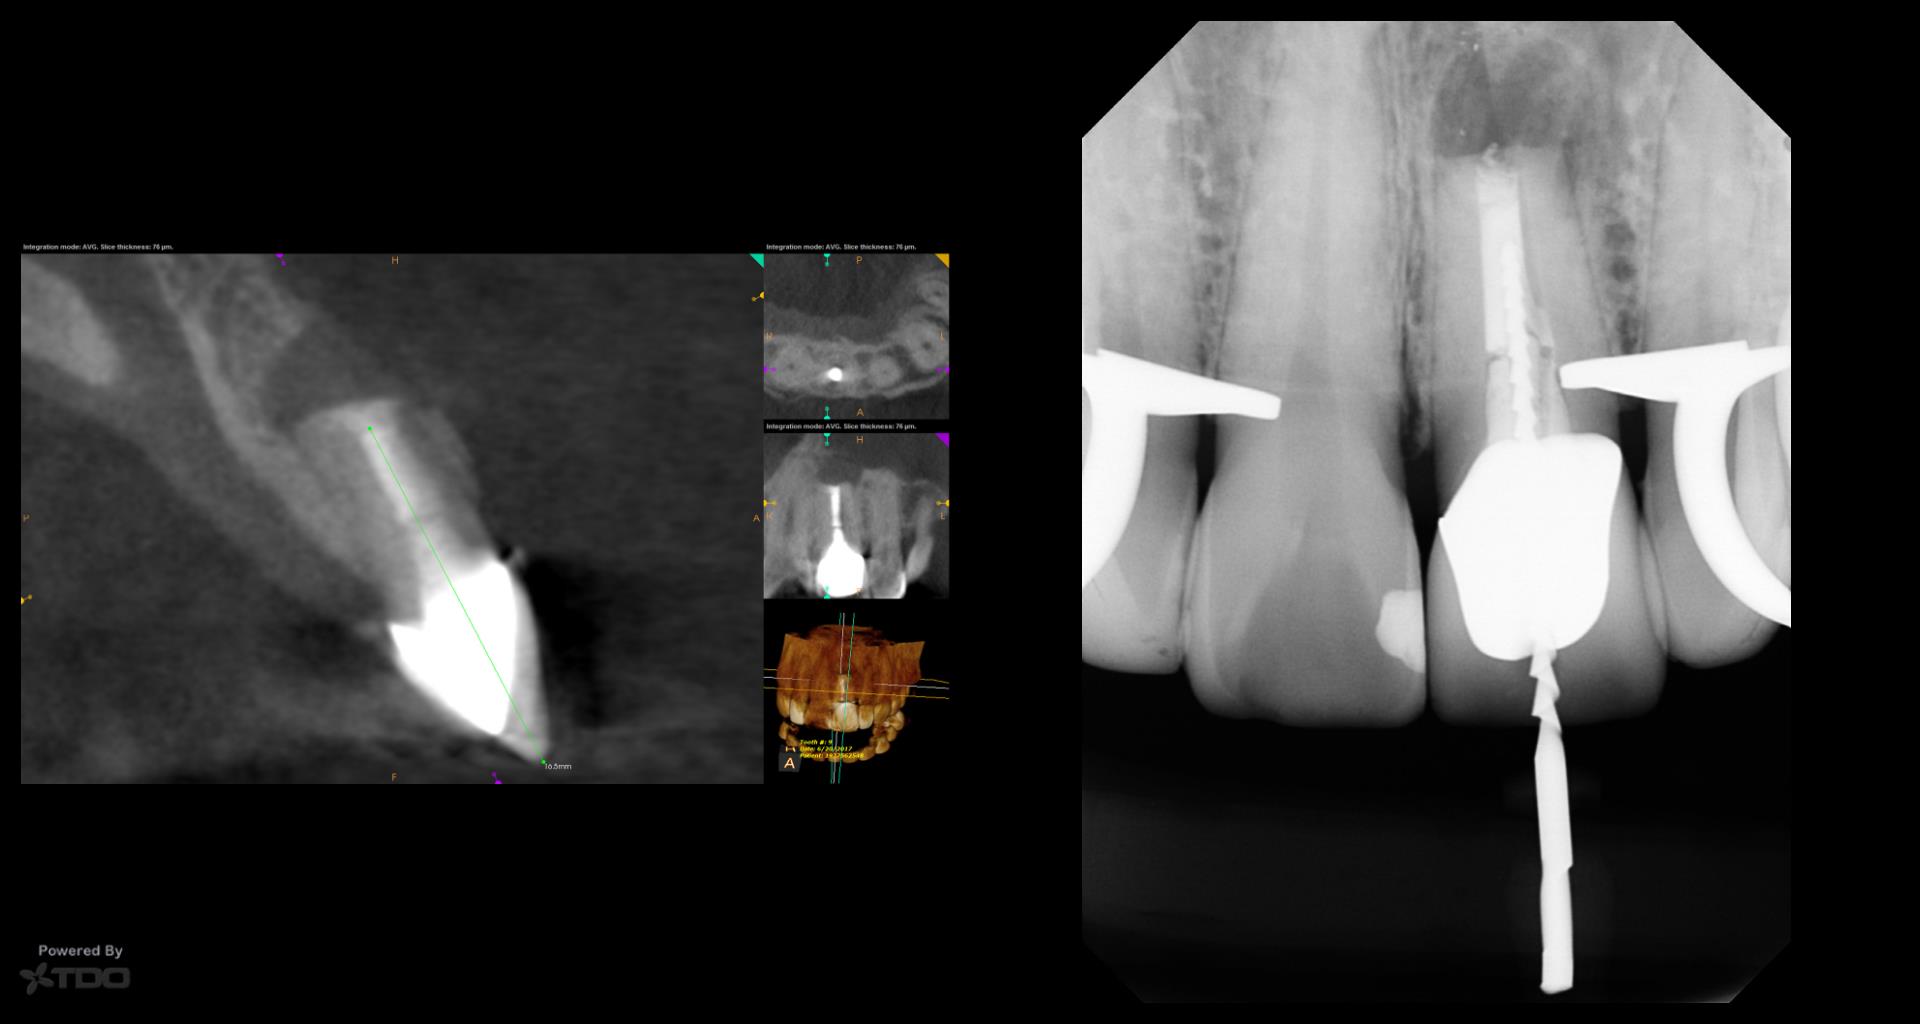

This was interesting because a root frac ture was seen where the prior apico was done. The MTAS was removed and Brassler putty used in this case. Will take a 1 yr CBCT and we will know more. Don’t usually get so much scar formation–so this was surprising…..